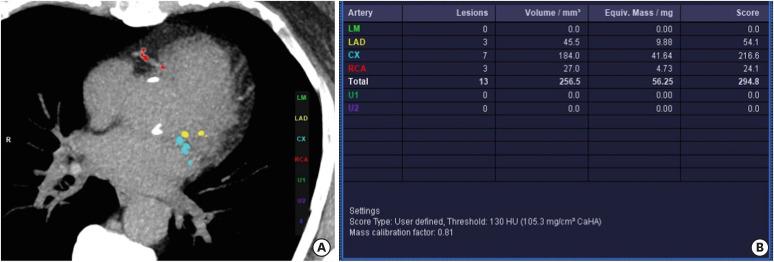

The Coronary Artery Calcium Data and Reporting System (CAC-DRS) is a standardized reporting method for calcium scoring on computed tomography. CAC-DRS is applied on a per-patient basis and represents the total calcium score with the number of vessels involved. There are 4 risk categories ranging from CAC-DRS 0 to CAC-DRS 3. CAC-DRS also provides risk prediction and treatment recommendations for each category. The main strengths of CAC-DRS include a detailed and meaningful representation of CAC, improved communication between physicians, risk stratification, appropriate treatment recommendations, and uniform data collection, which provides a framework for education and research. The major limitations of CAC-DRS include a few missing components, an overly simple visual approach without any standard reference, and treatment recommendations lacking a basis in clinical trials. This consistent yet straightforward method has the potential to systemize CAC scoring in both gated and non-gated scans.

冠状动脉钙化数据与报告系统(CAC-DRS)是一种用于计算机断层扫描中钙化评分的标准化报告方法。CAC-DRS是针对每位患者应用的,代表累及血管数量的总钙化评分。有4个风险类别,范围从CAC-DRS 0到CAC-DRS 3。CAC-DRS还为每个类别提供风险预测和治疗建议。CAC-DRS的主要优势包括对冠状动脉钙化进行详细且有意义的呈现、改善医生之间的沟通、风险分层、恰当的治疗建议以及统一的数据收集,这为教育和研究提供了一个框架。CAC-DRS的主要局限性包括一些缺失的部分、过于简单的视觉方法且没有任何标准参考,以及缺乏临床试验依据的治疗建议。这种一致且直接的方法有可能使门控和非门控扫描中的冠状动脉钙化评分系统化。